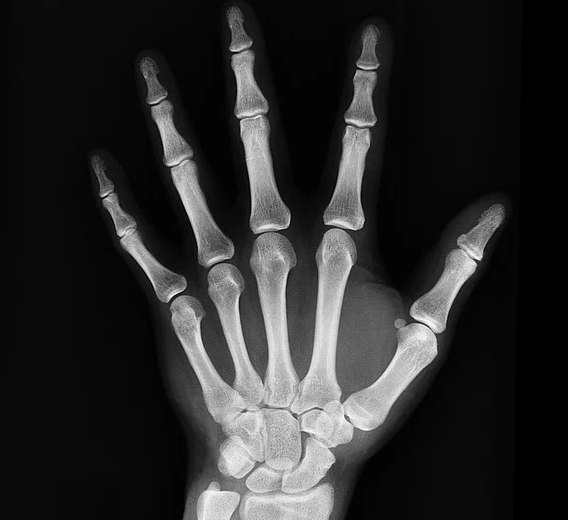

골다공증이란?

골다골증(骨多孔症) 이란 간략하게 말씀드리면 뼈의 강도가 약해져서 쉽게 골절되는 골격계 질환입니다. 우리의 뼈 조직은 끊임없이 죽고 다른 조직으로 바뀌는데, 매년 10% 가량이 새롭게 바뀌면서 10년이 지나게 되면 온몸의 뼈가 새롭게 바뀌게 됩니다. 낡은 뼈가 건강한 새뼈로 바뀌면서 건강한 뼈를 유지하게 되는 것이죠. 하지만 나이가 들어가면서 또는 폐경 후에는 뼈 밀도가 감소하면서 골 소실 속도가 높아지고, 골감소증을 거치며 골다공증까지 악화될 수 있습니다. 골다공증이 찾아온다면 가장 위험한 것은 뼈가 부러지는 골절인데요, 나이가 들어가면서 고관절 등 골절을 겪으면 목욕, 식사 뿐만 아니라 기본적인 의식주 생활 전체에 큰 불편함을 겪게 됩니다.